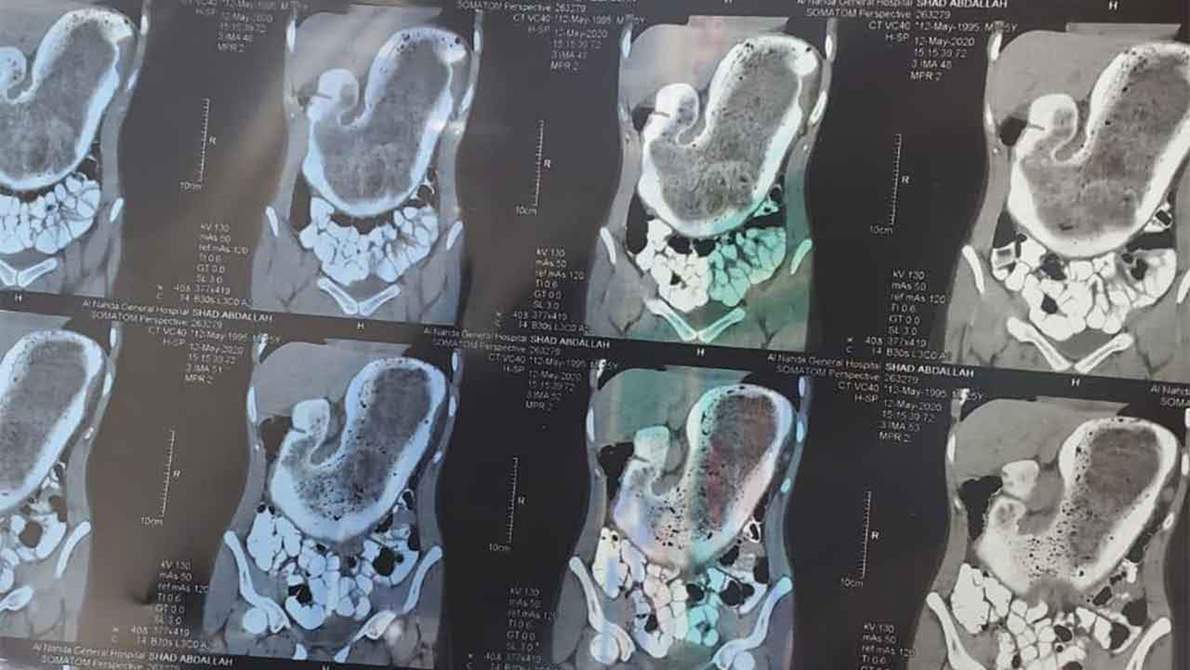

كشفت الفحوصات الطبية وجود كتلة من الشعر يقدر وزنها بـ 2.5 كيلوجرام في معدة فتاة تبلغ من العمر 17 عاما.

وقال المتحدث الرسمي لصحة المدينة المنورة: إن الفتاة ذهبت إلي المستشفى وهي تعاني من آلام في البطن وعدم احتمال الأكل والشرب، وبعد إجراء الفحوصات تبين وجود انسداد في تجويف المعدة، فتقرر إجراء عملية لاكتشاف سبب الانسداد، واتضح وجود كتلة من الشعر تجمعت في معدة الفتاة لعدة سنوات.

وأوضح المتحدث الرسمي لصحة المدينة المنورة أنه تم استخراج الكتلة على شكل أسطواني، ويقدر قطرها بـ9 سم وطولها 48 سم.